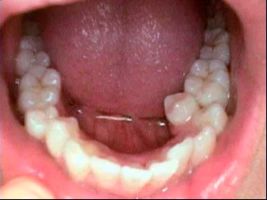

Invisalign

Before

After